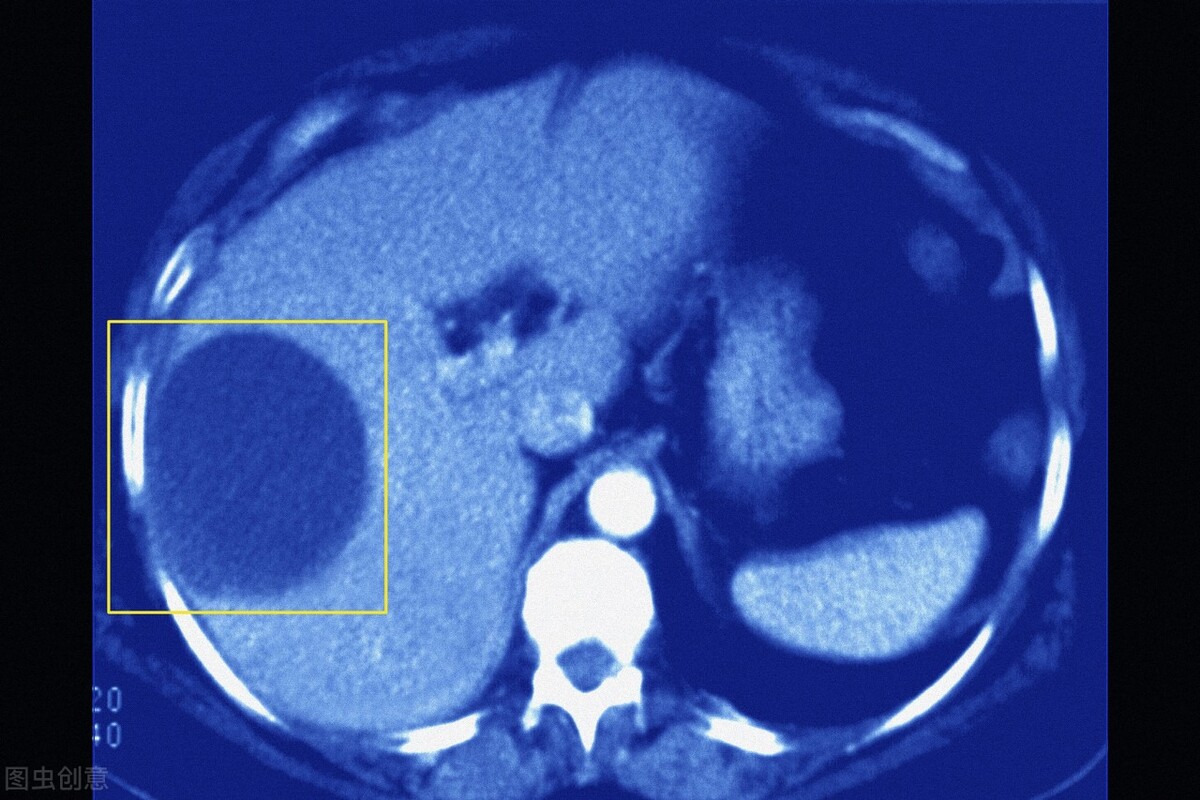

7、肝肾囊肿

很多人在进行B超检查时,都会发现肝脏或者肾脏中有囊肿。很多不明白的人,以为囊肿和癌症是一个意思,或者是认为囊肿能够演变为癌症,很是害怕。其实囊肿多数是因为先天性、炎症性或者创伤性而导致的,多数的囊肿直径较小,人体没有任何感觉,也无需治疗。不放心的可以定期进行影像学检查即可。

如果囊肿直径较大且出现压迫症状,那么是需要手术治疗的。